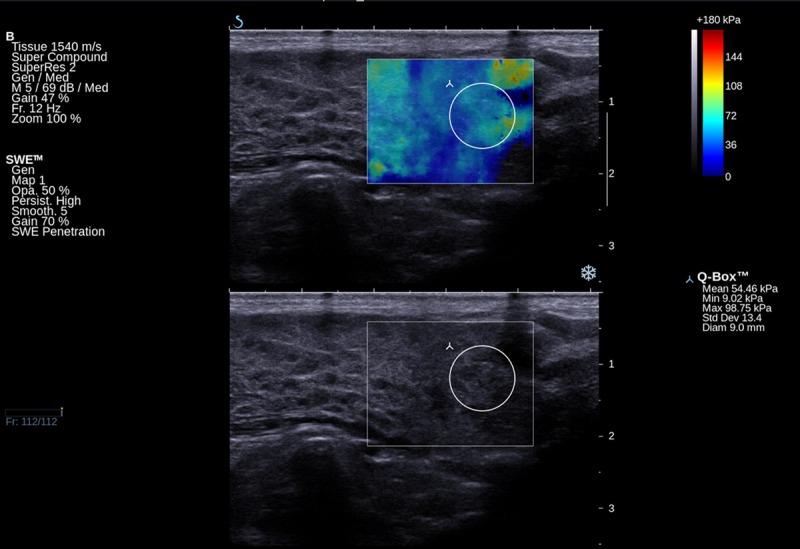

Shear wave elastography (SWE) is widely used in breast, liver, prostate and thyroid evaluations. Elastography provides additional information if used to assess parotid gland pathology. We assessed parotid glands by means of SWE to compare the parenchyma properties in different types of inflammation.

MATERIAL/METHODS: Prospective analysis included 78 consecutive patients with parotid gland pathology: sialolithiasis (33), Stensen's duct stenosis (15), chronic inflammation (10), and primary Sjögren syndrome (pSS) (20) treated at the Department of Otolaryngology, Head and Neck Surgery of PUMS. The primary predictor variable was type of parotid pathology, and secondary predictor variables were patient age and the duration and intensity of complaints. Ultrasound pictures were compared with elastography values of parotid parenchyma.

Mean elasticity values for pSS (111 Kilopascals (kPa), Stensen's duct stenosis (63 kPa), sialolithiasis (82 kPa), and chronic inflammation (77 kPa) were significantly higher than the mean value for healthy patients (24 kPa). Elasticity increased proportionally to the intensity of complaints: mild (51 kPa), moderate (78 kPa), and strong (90 kPa). Increased elasticity did not correspond with ultrasonographic pictures. In pSS the parenchyma was almost twice as stiff as in chronic inflammation (p=0.02), although subjective complaints were mostly mild or moderate, and the ultrasonographic picture did not present features of fibrosis.

剪切波弹性成像(SWE)广泛应用于乳腺、肝脏、前列腺和甲状腺的评估。如果用于评估腮腺病变,弹性成像可提供额外信息。我们通过SWE评估腮腺,以比较不同类型炎症中的实质特性。

材料/方法:前瞻性分析纳入了78例连续的腮腺病变患者,这些患者在PUMS头颈外科耳鼻喉科接受治疗,其中包括涎石病(33例)、腮腺导管狭窄(15例)、慢性炎症(10例)和原发性干燥综合征(pSS)(20例)。主要预测变量是腮腺病变类型,次要预测变量是患者年龄、症状持续时间和强度。将超声图像与腮腺实质的弹性成像值进行比较。

pSS的平均弹性值(111千帕斯卡(kPa))、腮腺导管狭窄(63 kPa))、涎石病(82 kPa))和慢性炎症(77 kPa))显著高于健康患者的平均值(24 kPa)。弹性与症状强度成比例增加:轻度(51 kPa)、中度(78 kPa)和重度(90 kPa)。弹性增加与超声图像不相符。在pSS中,实质硬度几乎是慢性炎症的两倍(p = 0.02),尽管主观症状大多为轻度或中度,且超声图像未显示纤维化特征。